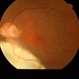

- choroidal coloboma

- Fundus camera

- Pre operative photo of a choroidal coloboma with retinal detachment.